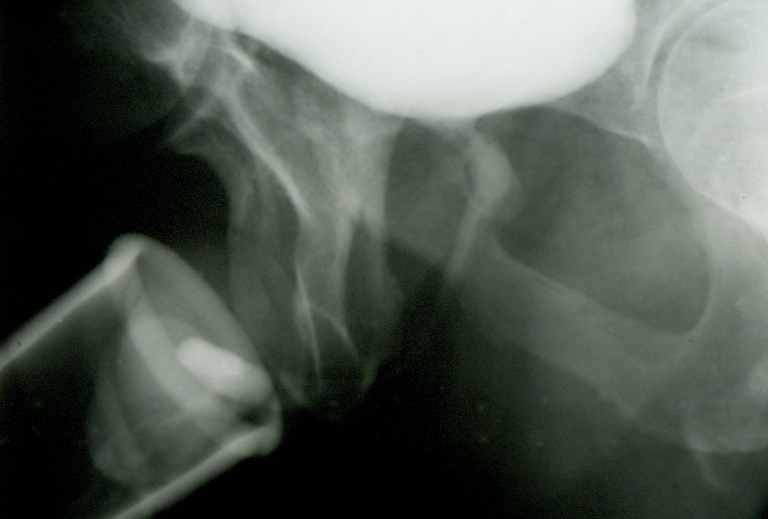

La radiographie pratiquée pendant

la miction montre une ouverture large (1,5 centimètre) de l'urètre prostatique

(B).

Les radiographies en série prises au cours de la miction, montrent

l'élargissement

en entonnoir

de

l'urètre prostatique. Le fait d'uriner correctement est intimement lié à

l'intégrité de la structure musculaire prostatique. L'excès de fibrose

ou les anomalies musculaires expliquent les difficultés mictionnelles

chez certains patients qui ne sont pas porteurs de tumeurs bénignes ou

malignes des éléments glandulaires.